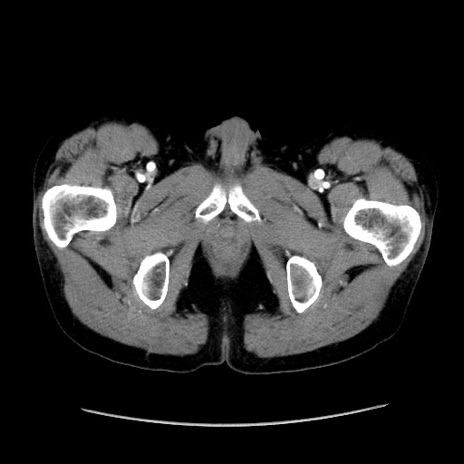

【症例】40歳代 男性

【主訴】腹痛

【現病歴】4時間ほど前に電車に乗車中に臍部上より腹痛出現。徐々に増悪し起立困難となり、救急外来受診。生ものは数日食べていない。今朝お雑煮を食べた。

【身体所見】BT 36.8℃、BP 117/84mmHg、HR 91/min、SpO2 97%、苦悶様、腹部:臍上部広範囲圧痛あり、反跳痛±

【データ】WBC 8100、CRP 0.03